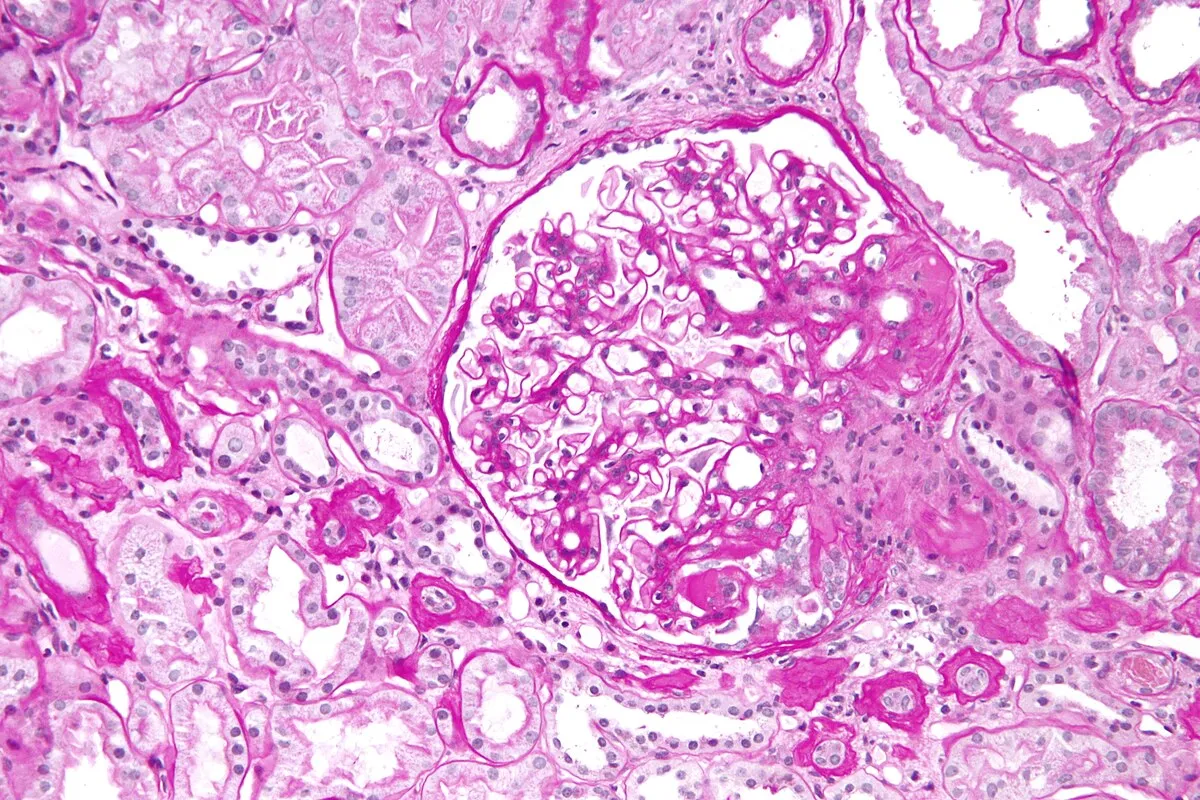

Injúria Renal Aguda (revisão Lancet 2025)

Injúria Renal Aguda (revisão Lancet 2025)